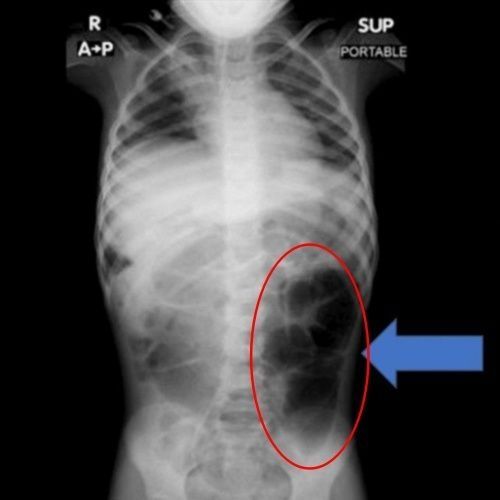

위장에 포착된 머리카락 덩어리. 큐레우스 캡처

의료진이 A양의 위장을 정밀 검사한 결과, 위 내부에 머리카락이 엉켜 형성된 덩어리가 발견됐다. 머리카락은 위장에만 머무르지 않고 소장까지 이어진 상태였다. 의료진은 "소아 환자에게서 반복적인 복통, 구토, 식욕 저하 등이 장기간 지속되면 위장관 내 이물질의 존재 가능성을 반드시 고려해야 한다"고 강조했다.